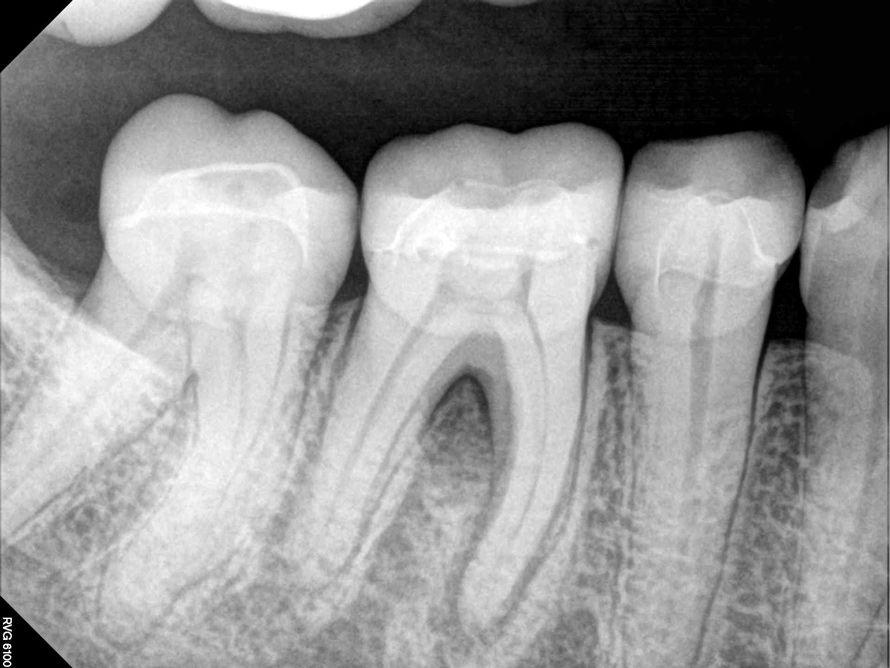

Fig 9. It is clinically acceptable to have results with the sealer puff (Figure 9) and without (Figure 10).

Figure 9

Fig 10. It is clinically acceptable to have results with the sealer puff (Figure 9) and without (Figure 10).

Figure 10

The sealer puff achieved by any method is the stuff of lore among endodontic residency programs. Certain schools of thought (and schools) find it to be the marker of successful treatment, in that it proves a complete seal to the apex.18 Others argue that it represents a foreign body that could create long-standing inflammation resulting in impaired healing.20 Certainly, one could argue against a puff of sealer in cases when the root apices are in contact with the mandibular nerve, but in most cases the presence or absence of a sealer puff has not been shown to create an inflammatory reaction (Figure 9 and Figure 10). This will likely remain an area of controversy for as long as there are dentists doing endodontics.